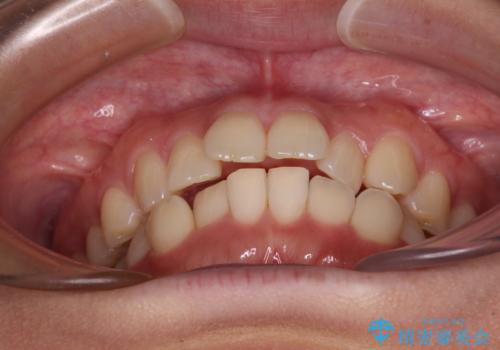

上下前歯のデコボコ ワイヤー装置で楽して改善

- 上下前歯のデコボコを気にして来院された患者様です。

ワイヤー矯正でもインビザラインでも、どの装置でも対応可能でしたが、安価で楽して素早く治療を終えたいとのことで、メタルブラケット装置による矯正治療を行うこととしました。